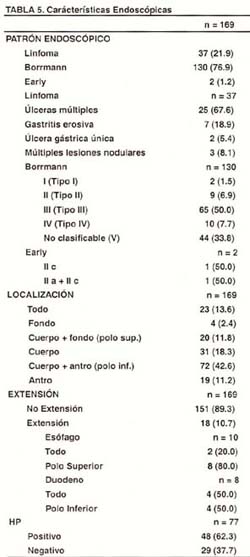

En la Tabla N° 5, se analizan las características endoscópicas de los pacientes con Linfoma Gástrico. El patrón endoscópico se ha divido en tres partes respecto al diagnóstico al ingreso de los pacientes, esto es: diagnóstico de Linfoma Gástrico, diagnóstico de cáncer gástrico avanzado tipo Borrmann y diagnóstico de cáncer gástrico temprano o early. Se identifica claramente que la predominancia de los pacientes con Linfoma Gástrico, pertenecen al denominado cáncer avanzado tipo Borrmann (76.9%). De la misma manera, el patrón endoscópico correspondiente al Linfoma Gástrico corresponde aproximadamente a 1 de cada 5 pacientes diagnosticados y el aspecto del tipo early fue identificado sólo en 2 casos. El patrón endoscópico del Linfoma a su vez fue dividido de la siguiente manera: úlceras múltiples, gastritis erosiva, úlcera gástrica y lesiones nodulares. Las úlceras múltiples son las más frecuentes dentro del presente patrón endoscópico (67.7%), y probablemente sean las lesiones más representativas de esta entidad para hacer con certeza un diagnóstico precoz de la misma.

Cuando se analiza el aspecto del Linfoma Gástrico diagnosticado al ingreso como cáncer gástrico avanzado tipo Borrmann, el aspecto de la neoplasia maligna tipo Borrmann III, es el más frecuente con el 50% de los casos, seguido del tipo No Clasificable (tipo V, según la denominación Japonesa), con el 33.8% de los mismos. El aspecto del cáncer gástrico tipo Early o Temprano para el Linfoma Gástrico, incluyó en la presente serie a dos pacientes, ambos con lesiones básicamente deprimidas tipo IIC (mixta una de ellas). La localización del Linfoma Gástrico es más frecuente en el cuerpo, sea de manera individual (18.3%), o de manera combinada, tanto en la forma del polo superior (11.8%), como del polo inferior (42.6%), respectivamente. A fin de encontrar la localización que con mayor frecuencia se encuentra en el Linfoma Gástrico, hemos reunido a todos los pacientes que tienen más de una localización con los que tienen una sola, siendo la probabilidad de compromiso del cuerpo respecto al antro de 123/91. El compromiso de todo el estómago alcanza el 13.6% y el compromiso exclusivamente del antro, llega al 11.2%. La extensión de la enfermedad a esófago se da en 10 pacientes y a duodeno en 8 pacientes, no teniendo dicha característica la mayoría de los pacientes que representaron el 89.3%. Finalmente, de los 77 pacientes evaluados en búsqueda del helicobacter pylori, se encontró positividad en el 62.3%, siendo negativos para Helicobacter pylori el 37.7% de los pacientes.